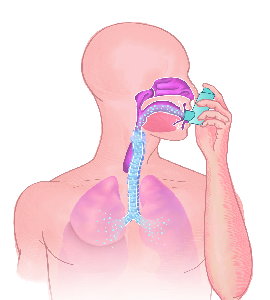

Detailreiche Fotografien aus der medizinischen Praxis ergänzen die Texte; moderne, genaue,

wissenschaftliche Zeichnungen geben Einblick in die Anatomie und die Funktion der Lunge und

anderer Organe.